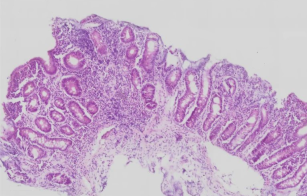

Small intestinal biopsy from child

Previous research that analysed EE biopsies histologically showed that in the small intestines of those with EE, the villi — structures that absorb nutrients from food — are shorter. It was also found that the gut’s barrier functions are responding in a pattern that resembles an attempt to keep harmful bacteria out, but which has the side effect of preventing nutrient absorption.